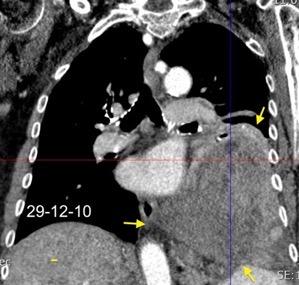

Síndrome de afectación postcardiaca (postcardiac injury)

Post infarto 1-7 % (Dressler)

Trauma cerrado Implantación marcapasos

Cirugía cardiaca. 17-31% (Post.pericardiotomía)

3707 pacientes 29 Derrames (0,78%) > de 25% del hemitórax

Todas menos 2 Izdos.

Angioplastia

By-pass coronario 21-10-03